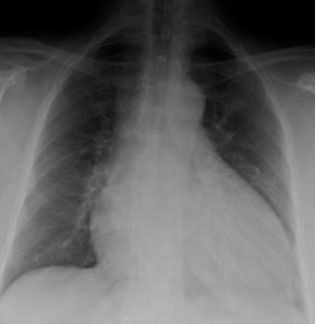

Dilated cardiomyopathy

MCC cardiomyopathy (90%); MCC heart transplantation; 3rd MCC heart failure [2]

Progressive cardiac hypertrophy, dilation, systolic dysfunction

- laterally displaced apical impulse, narrow pulse pressure, bundle branch blocks (cause arrhythmias that lead to edema and pleural effusions)

Gross: enlarged, flabbly heart, over 900 g, all 4 chambers dilated, ventricles > atria

- explains the systolic dysfunction, with a failing EF (<40%), S3

Imaging: Balloon-heart on cxr

Micro: nonspecific, myocyte hypertrophy, interstitial fibrosis, wavy fiber change or myofiber loss, scanty mononuclear inflam infiltrate

- Eccentric hypertrophy (sarcomeres added in series) --> vol overload